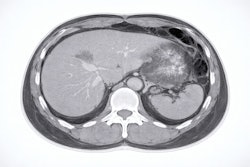

Battlefield medicine distinguishes three roles, according to Graham. Role 1 involves primary care near the point of injury, where point-of-care ultrasound is used most often. Role 2 involves enhanced intermediate care at field clinics, where dynamic digital radiography (DDR) x-ray and ultrasound are key. Role 3 advances care to a specialized hospital model where ultrasound and DDR x-ray are used, but CT is best, he noted.

Black swan events have occurred around the world, Gilligan explained. When a terror truck was used to attack pedestrians in Nice, France, in 2016, healthcare services conducted 42 CT exams on 42 patients during a two-hour period. In another example, a majority of the tourists involved in a 2016 vehicle collision in Seattle, WA, underwent whole-body CT. Importantly, an earthquake in New Zealand in 2011 led to 21 CTs in six hours -- after a five-hour delay from power outages.

"Power and other infrastructure isn't guaranteed, and that's when we need solutions on the fly," Gilligan said. He listed considerations useful for CT scanner planning in emergency preparedness:

- Table length and weight capacity (tables that can take heavy patients with large, rapid feed)

- Wide bore sizes (>70 cm) and large room sizes (minimum 50 m2)

- High tube heat capacity and dissipation so that tubes do not overheat between patients

- Detector warmup time (can be up to 30 minutes, problematic in emergencies)

- Parallel processing of reconstructions

- Availability of local advanced image processing and storage (imaging networks may not be guaranteed)

- Operating temperatures of scanners (ranges in relation to room cooling requirements)

- Power consumption of CT scanners (simulate and plan in advance)

- Availability of an uninterruptible power supply